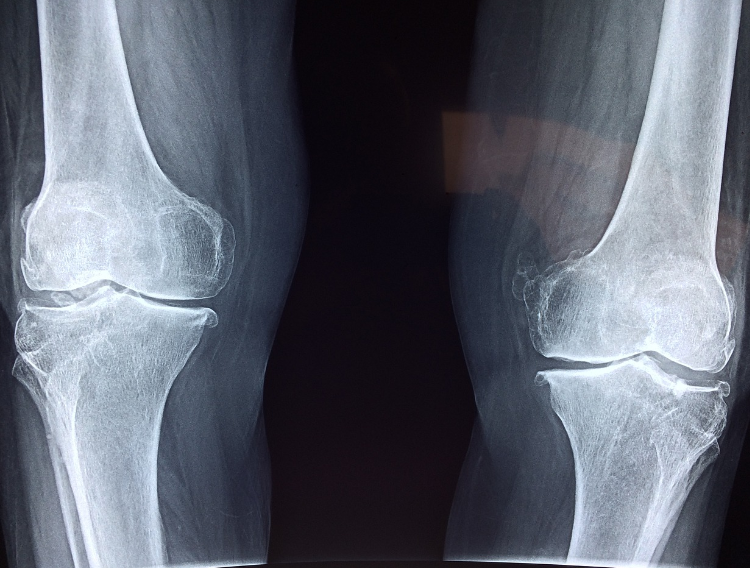

Get to the root with a chiropractor

A holistic approach means addressing your health concerns through more than medical treatments alone, and one that has become more popular and widespread as of late is the chiropractic approach. With the help of a primary care physician specialising in chiropractors, you may be able to address some of the root causes of physical pain, such as misalignment or inflammation. This approach has been found by many to be able to tackle the sources of issues such as joint pain, poor circulation, migraines, and more. It can also offer long-term relief to pain without the need for medication, which can help some people wean themselves off of medicine that they have a risk of becoming dependent on. You can search for chiropractors online. Check out websites such as this one from Dr. John Heary and compare services.